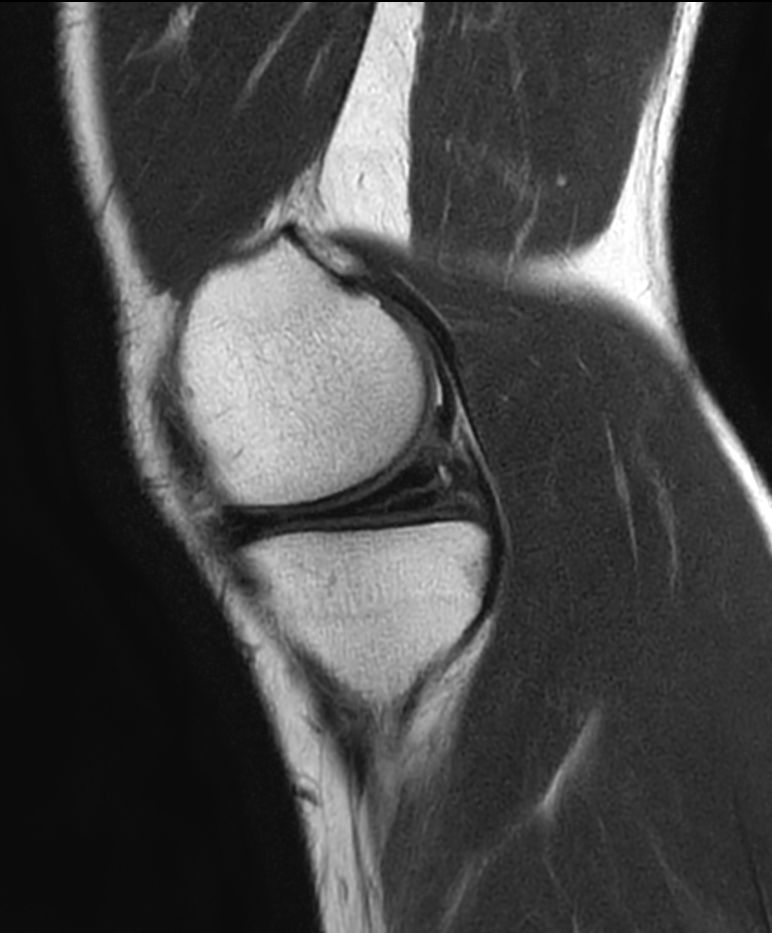

PDw TSE - Compressed SENSE